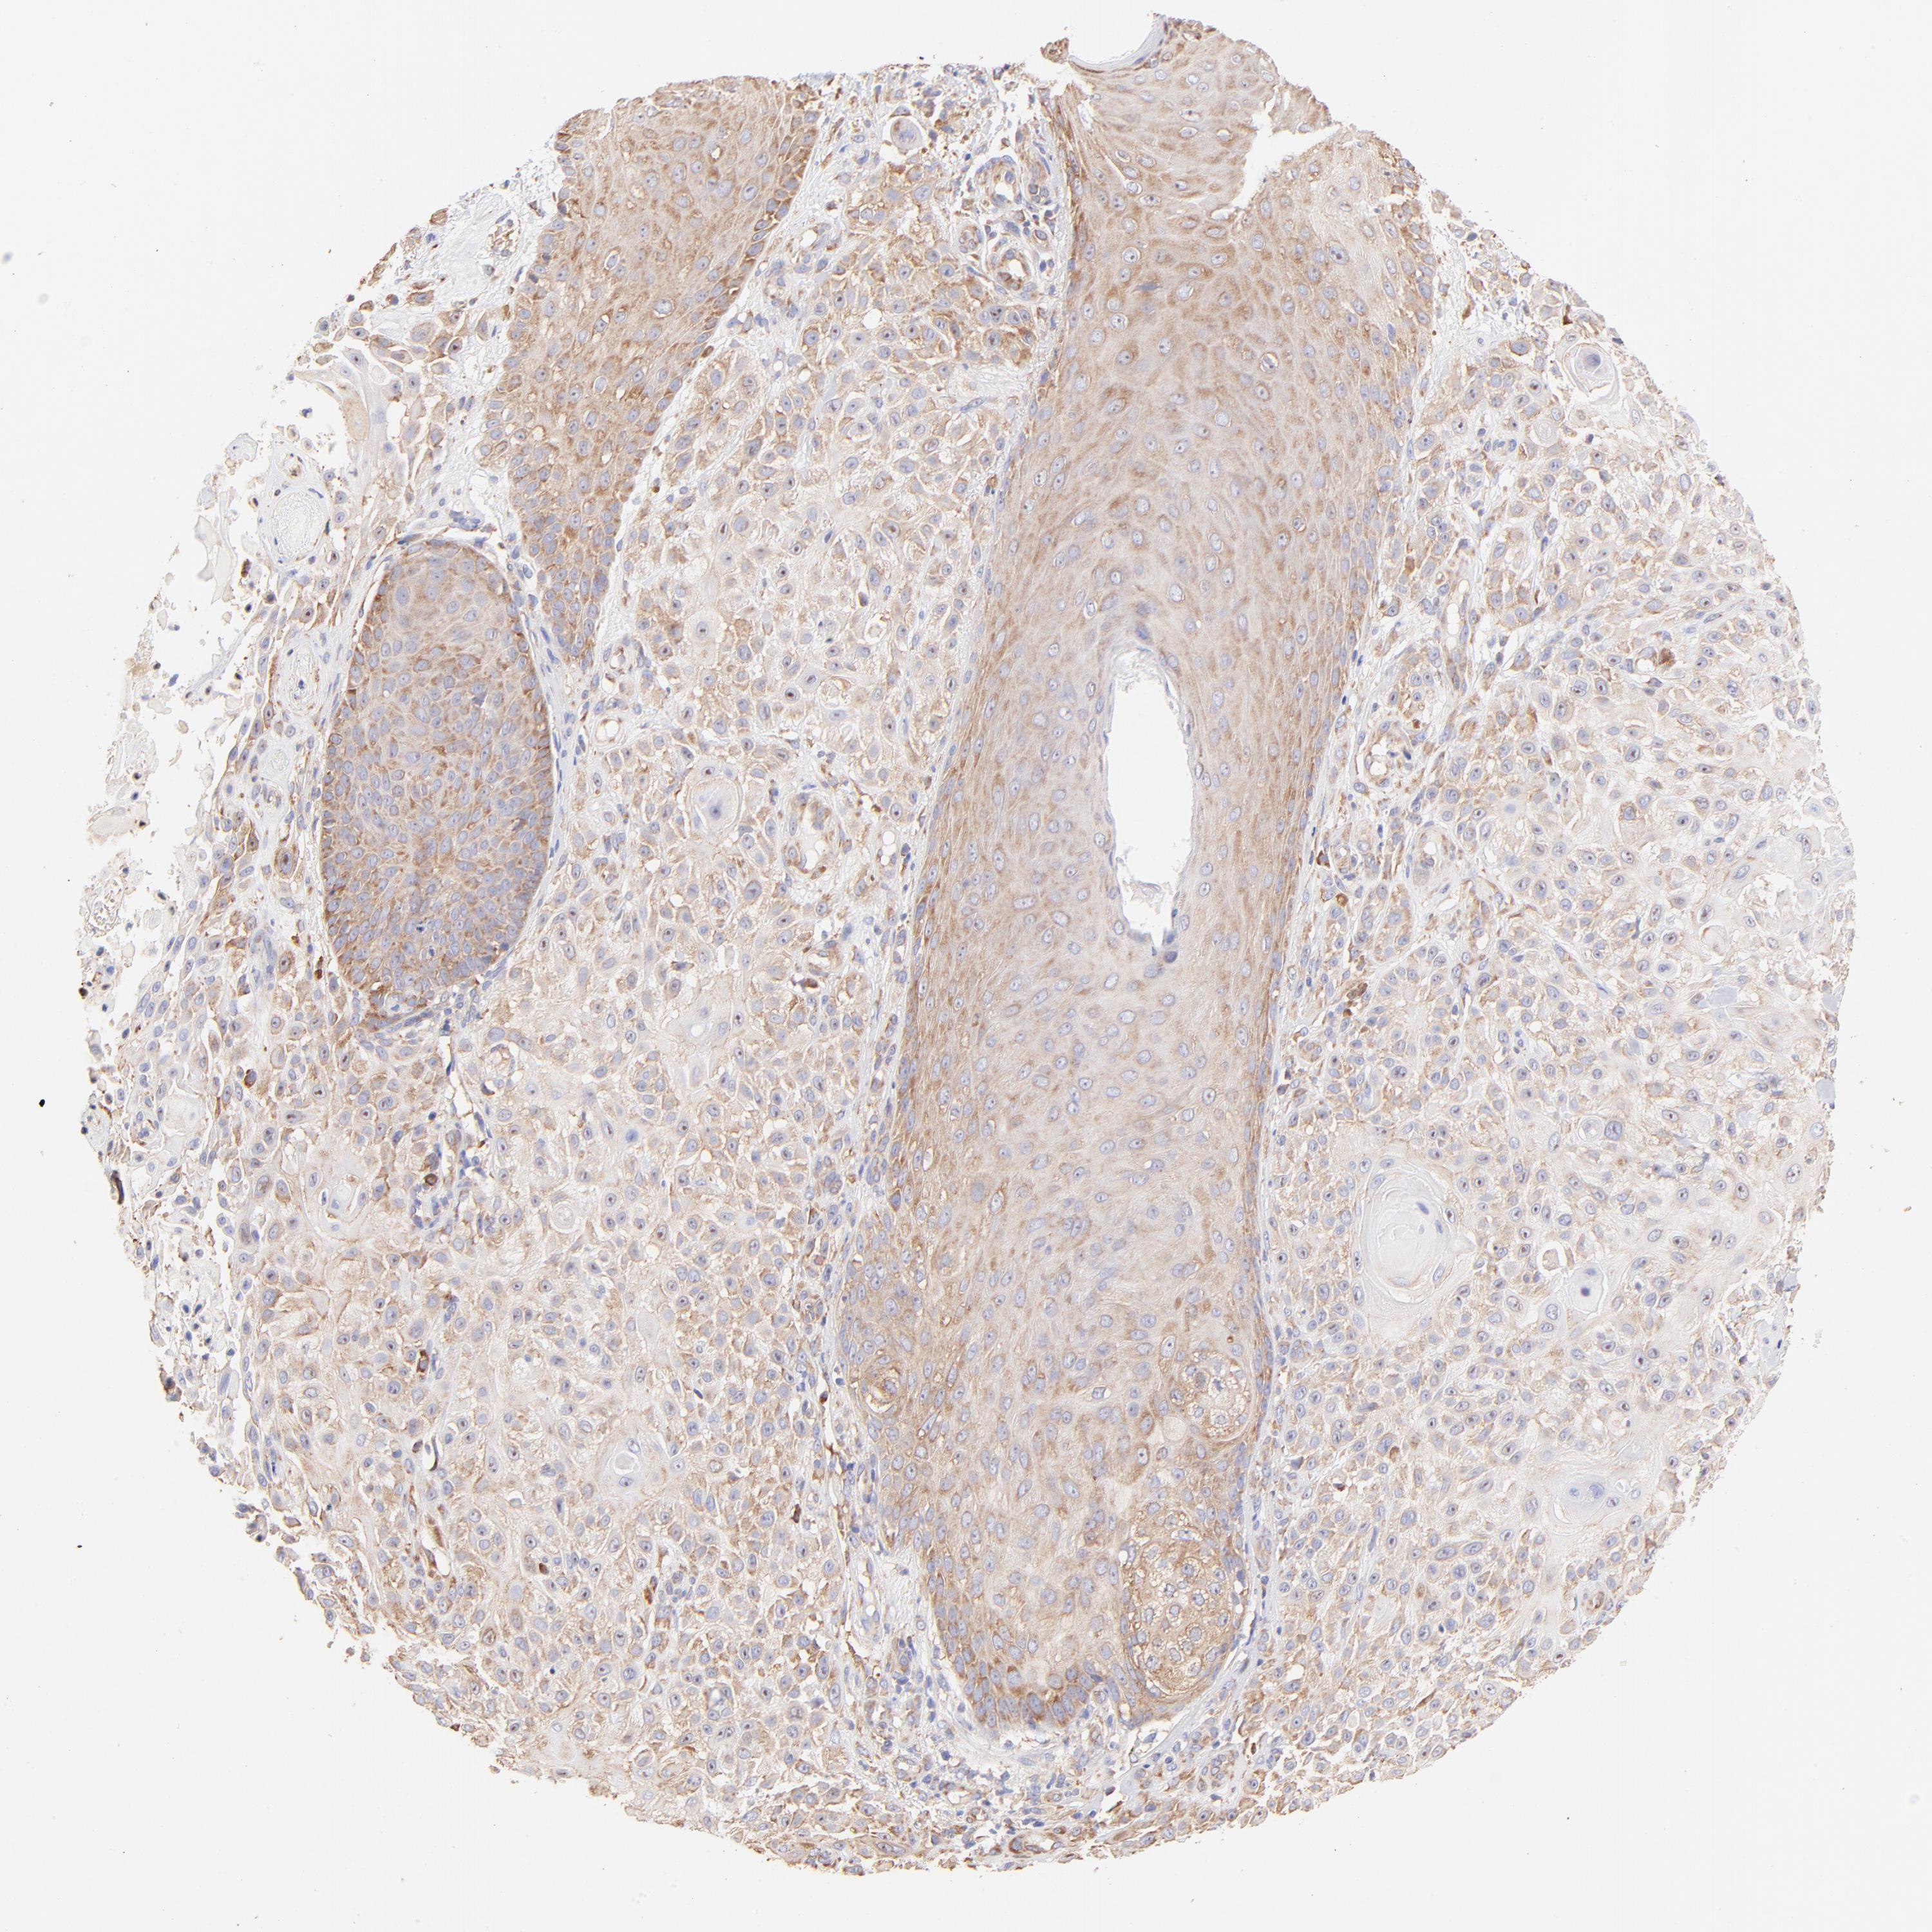

SKIN CANCER - Protein expressioni

A mouse-over function shows sample information and annotation data. Click on an image to view it in a full screen mode. Samples can be filtered based on level of antibody staining by selecting one or several of the following categories: high, medium, low and not detected. The assay and annotation is described here.

Antibody stainingi

Antibody staining in the annotated cell types in the current human tissue is reported as not detected, low, medium, or high, based on conventional immunohistochemistry profiling in selected tissues. This score is based on the combination of the staining intensity and fraction of stained cells.

Each image is clickable and will lead to virtual microscopy that enables deeper exploration of all samples and also displays staining intensity scores, fraction scores and subcellular localization as well as patient and tissue information for each sample.

Antibody HPA002651

Staining

High

Medium

Low

Not detected

Intensity

Strong

Moderate

Weak

Negative

Quantity

>75%

75%-25%

<25%

None

Location

Nuclear

Cytoplasmic/membranous

Cytoplasmic/membranous,nuclear

Squamous cell carcinoma, NOS